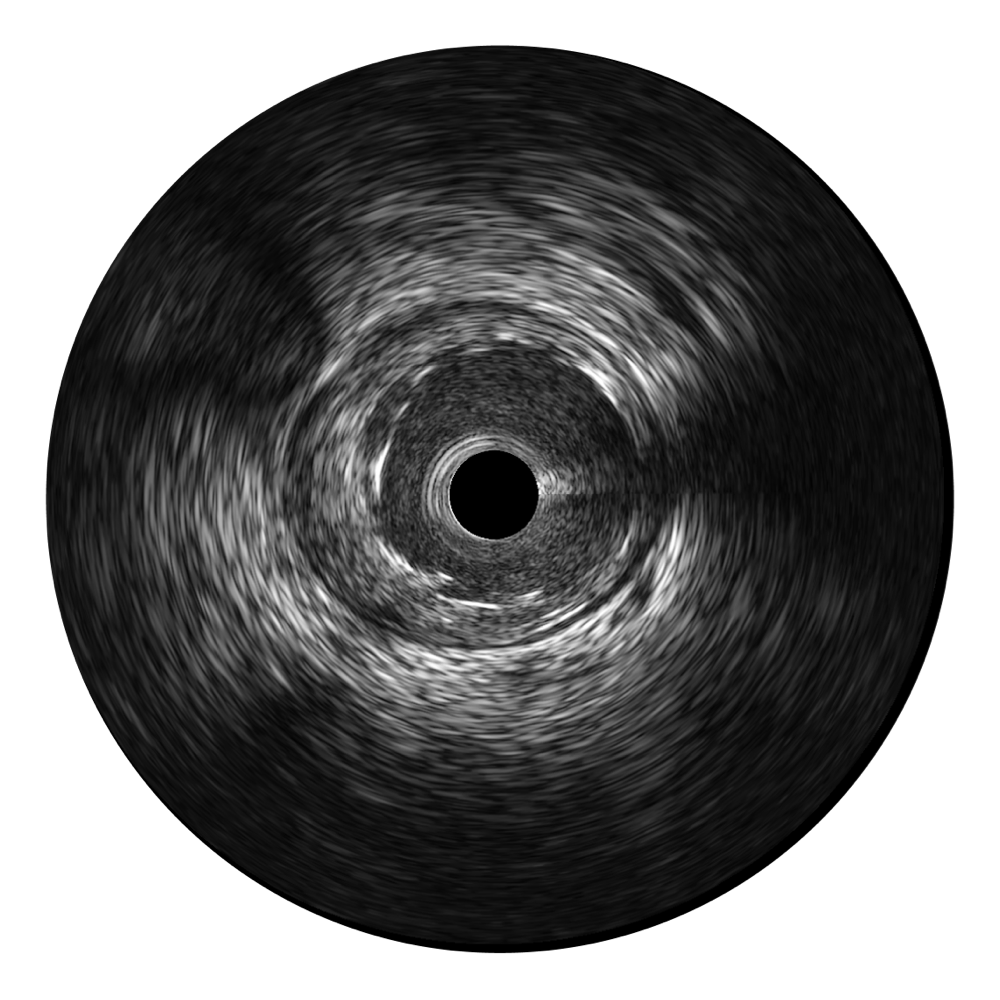

狗万官方网站宽频IVUS图像

传统IVUS图像

对比传统IVUS导管成像,狗万官方网站宽频IVUS图像的近场支架梁显影更细腻,远场中膜外血管仍清晰可辨,兼顾远中近,兼顾分辨力与穿透深度